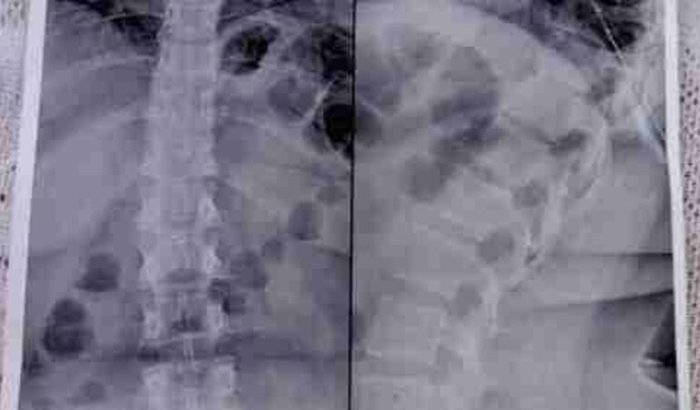

Escoliose acompanhada de Hiperlordose Lombro Sacra   ver tudo

Escoliose acompanhada de Hiperlordose Lombro Sacra